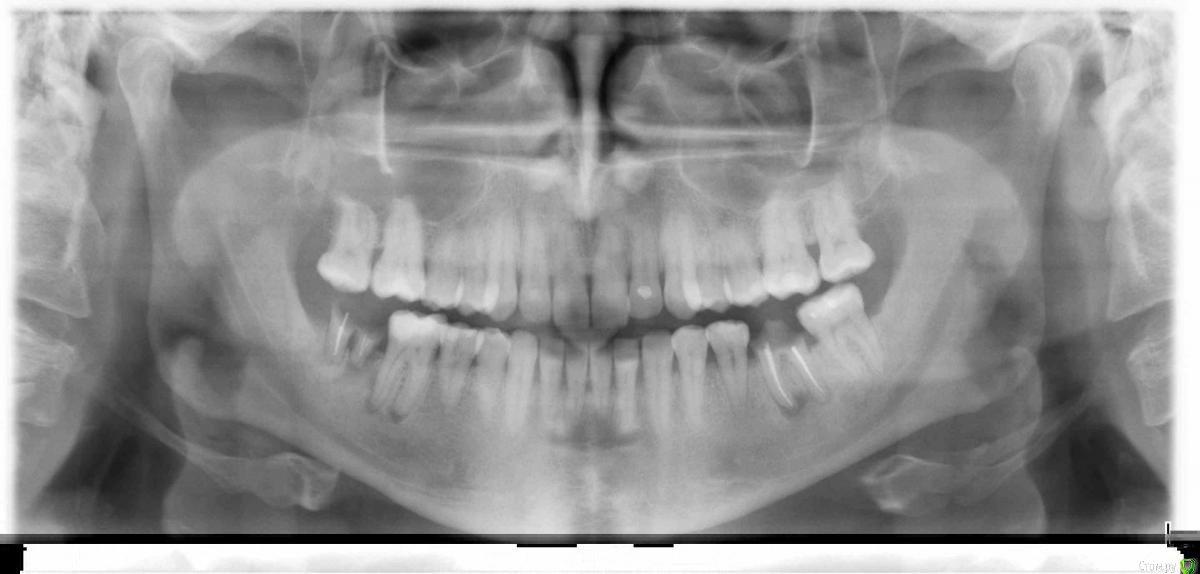

besyaka Опубликовано 21 ноября, 2016 Поделиться Опубликовано 21 ноября, 2016 Здравствуйте! Помогите определить по снимку что лечить, а также на нижней шестерке справа пульпит или нет? Доктор говорит пульпит четыре канала, но зуб не беспокоит, не разрушен, единственное ,что такое ощущение, что как будто немного пошатывается Ссылка на комментарий

red_butler Опубликовано 21 ноября, 2016 Поделиться Опубликовано 21 ноября, 2016 в смысле?Был пульпит, а сейчас хронический апикальный периодонтит. Ищите врача и лечите каналы. Корни удаляйте. 1 Ссылка на комментарий